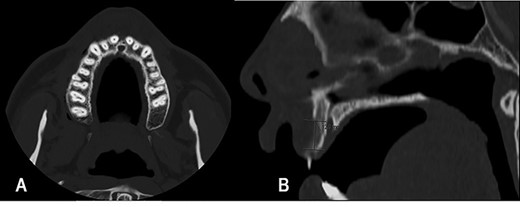

On examination, a lobulated, firm mass was seen extruding from the anterior maxillary vestibule (Fig. 1). All maxillary teeth were painless to percussion, and normal tooth mobility was present. No cervical lymphadenopathy was detected, nor any changes with cranial nerve examination. A maxillofacial computerized tomographic (CT) scan revealed an osteolytic lesion on the maxillary alveolar process (Fig. 2).

Maxillofacial CT scan, axial (A) and sagittal (B) images. Osteolytic lesion on the vestibular edge of the maxillary alveolar process, with 12 mm of craniocaudal dimension and 4 mm of axial dimension.